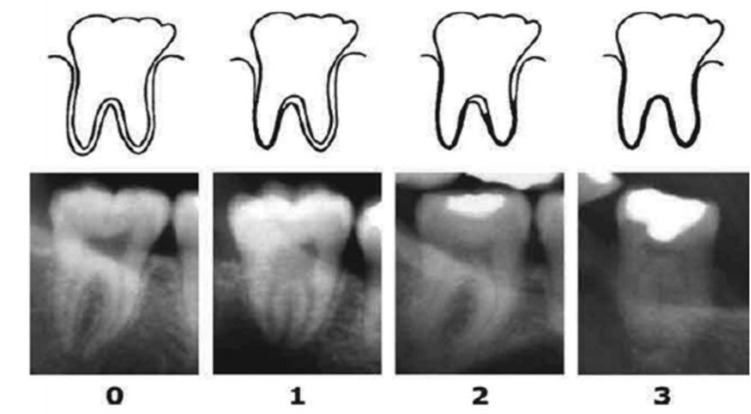

Methodology: A retrospective assessment of 202 OPGs was done to review the visibility of the periodontal ligament of third molars with completed root formation according to the methods described by Olze et al (2010). Individual ages were then calculated by deducting date of exposure from the date of birth recorded in years. Mean age with standard deviation were calculated for each group.

Results: Assessing the minimum and maximum age at which each of the stages of the radiographic visibility of the periodontal ligament as seen on the OPGs revealed that there was a gradual increase in the age at which the stage increment occurred, with a few exceptions. Comparison of the radiographic visibility of the periodontal ligament revealed that males tend to achieve early periodontal visibility stages compared to females, but the reverse was observed in later stages. Age 17 is more than likely attained in any person found within stages 1 to 3 as the minimum age found in these stages were above 17 years.